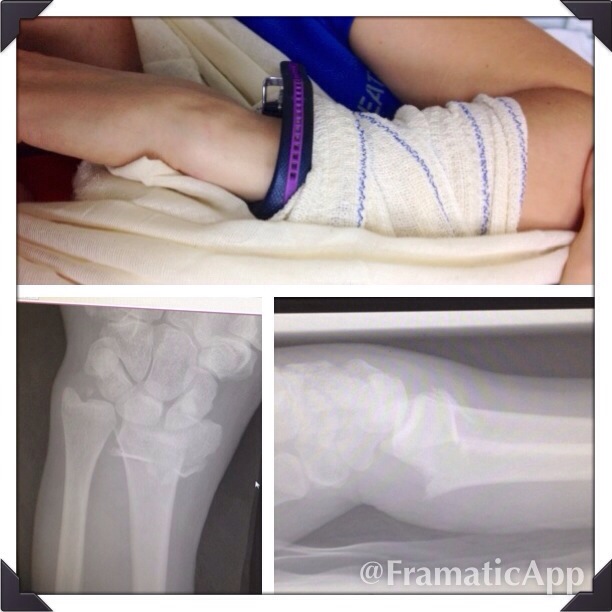

Now that we’ve cleared that up, we can officially celebrate the exactly 2 month anniversary of turning this pull up fall:

Into my new superhuman arm!

Yes, today is 2 months post foreign country surgery. And while it’s all cool be bionic and I’ve gotten over my relatively suicidal looking scar, it’s even cooler to realize how much different today would be had I opted for the 8 wk, we’ll hope it heals correctly, cast method originally suggested.